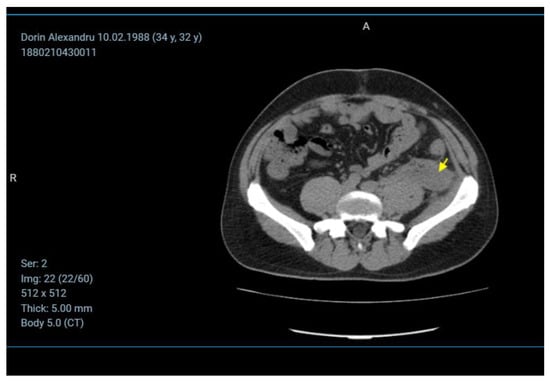

Case Presentation

- Imaging